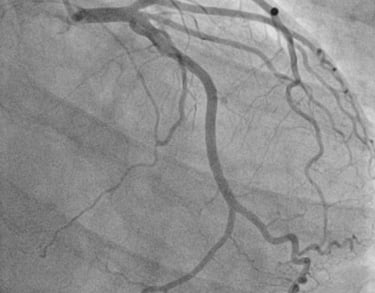

CORONAROGRAFIA

La Coronarografia è l’esame piu’ approfondito per valutare la presenza di restringimenti (“stenosi”) a carico delle arterie coronarie, ovvero delle arterie che nutrono il cuore. Viene effettuata tramite utilizzo di appositi cateteri che vengono inseriti attraverso l'arteria radiale o femorale. Per acquisire le immagini viene utilizzato un liquido chiamato “mezzo di contrasto” che opacizza il lume delle arterie mescolandosi al sangue. Le immagini vengono acquisite da un macchinario che emette una debole radiazione e registra le immagini.